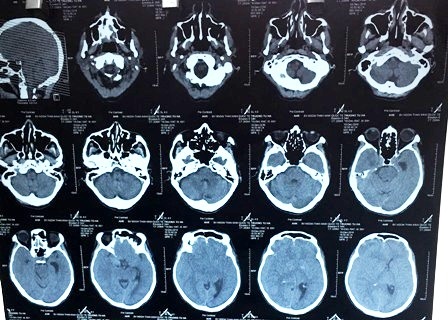

Kết quả chụp CT-scan đầu xác định, người bệnh bị máu tụ dưới màng cứng mạn tính ở cả 2 bán cầu, bên phải nhiều hơn bên trái. Tình trạng máu tụ đẩy lệch đường giữa (khoảng 11mm), chèn ép não thất bên phải (nguyên nhân gây yếu liệt nửa người bên trái). Bên cạnh đó, kết quả X-quang phổi ghi nhận, bệnh nhân bị xơ phổi trên nền bệnh lao phổi cũ.